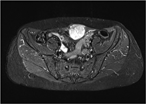

First reported case of paratesticular seminoma in a postpubertal cryptorchid testis

Imad Elhajjar and others

Journal of Surgical Case Reports, Volume 2017, Issue 6, June 2017, rjx088, https://doi.org/10.1093/jscr/rjx088